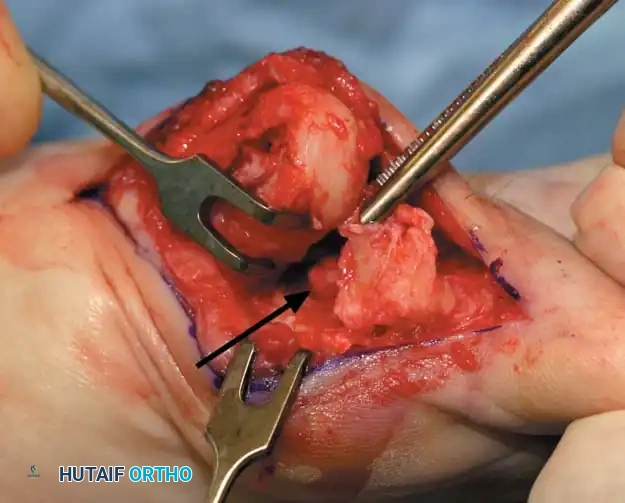

• Remove the base of the proximal phalanx at the metaphysealdiaphyseal junction, which usually constitutes the proximal third of the phalanx (Fig. 78-30A and B). To prevent damage to the fl exor hallucis longus and the neurovascular bundles, place a retractor over the bone dorsally and plantarward, and rotate the phalanx into view. Also, do not allow the saw blade to exit bone more than 1 to 2 mm.

• When the osteotomy has been completed, grasp the basilar fragment with a small Kocher clamp or towel clip, and rotate the fragment while applying medial pull to excise it. Lift it away from its lateral attachments, which are primarily the lateral collateral ligaments and the adductor muscle tendinous insertion (Fig. 78-30C).

Fig. 78-30 Keller technique. A, Re section of proximal phalanx, release of adductor tendon, and resection of medial eminence. B, Metaphyseal-diaphyseal junction of proximal phalanx (arrow) . C, Note concave plantar aspect of proximal phalanx for course of fl exor hallucis longus tendon (arrow) .